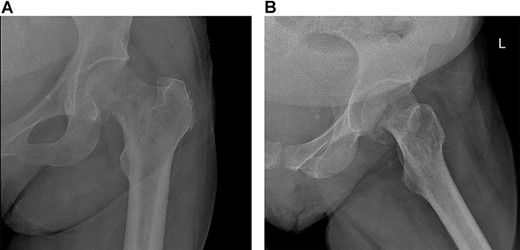

The patient was then referred to an outpatient physical therapy center to resume her physiotherapy. The patient achieved full weight bearing and excellent range of motion within 2 months postoperatively. Implants remained in good position showing no signs of loosening on x-rays (Fig. 4) on the ninth month visit, and she denied any pain with walking and had excellent range of motion at the time.

(A) Left (L) view of the implant in position; (B) Pelvic X-ray showing the implant in position.